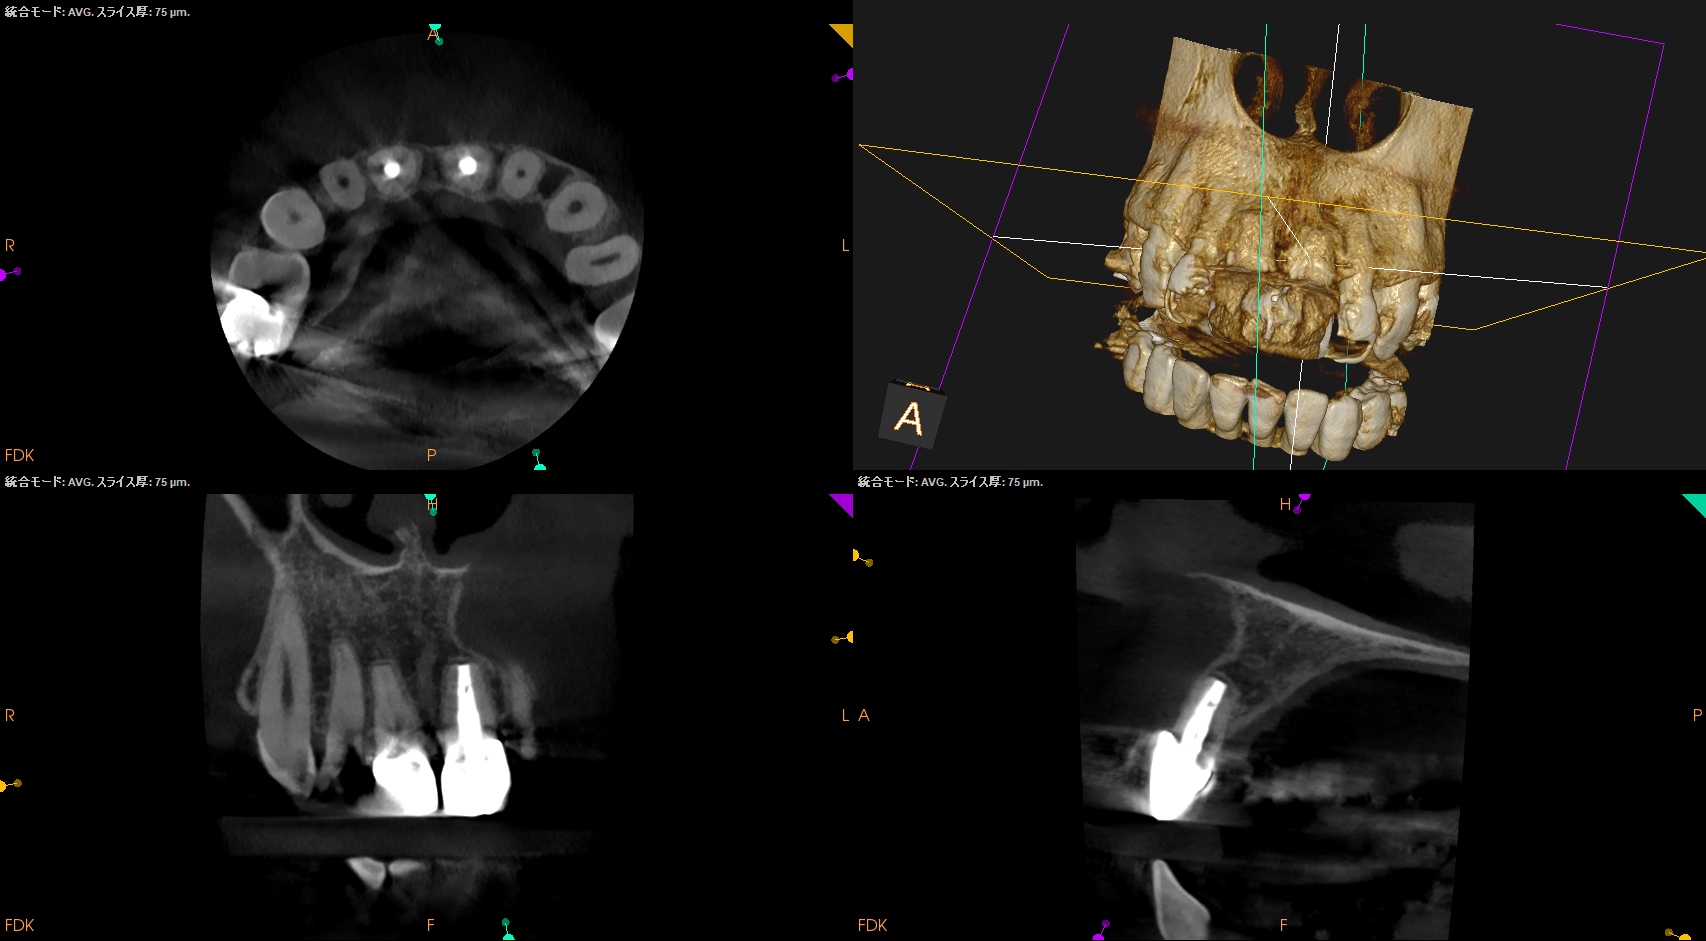

前歯の根元に膿が溜まっていると言われ、抜歯が必要と言われたが抜きたくない。残せないだろうか?〜#8,9 Apicoectomy

#8は通常通り3mm,

#9は歯根の外部吸収があるため臨在歯を考慮しApexから1mmのみ切断して行ったApicoectomy

から1年が経過した。

#8,9 Apicoectomy 1yr recall(2025.10.8)

術後と比較した。

術前の問題は消失した。

#9はやはり術前の予想通り1mmの切断で事足りた。